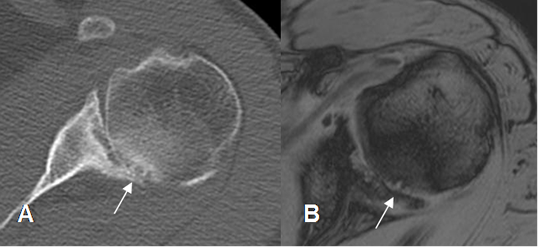

Fig 95. Pinzamiento postero-superior.

A: TAC axial y B: RM axial en FFE. Cambios degenerativos en la parte posterosuperior de la articulación glenohumeral, con pérdida del espacio, esclerosis y quistes subcondrales, por pinzamiento.